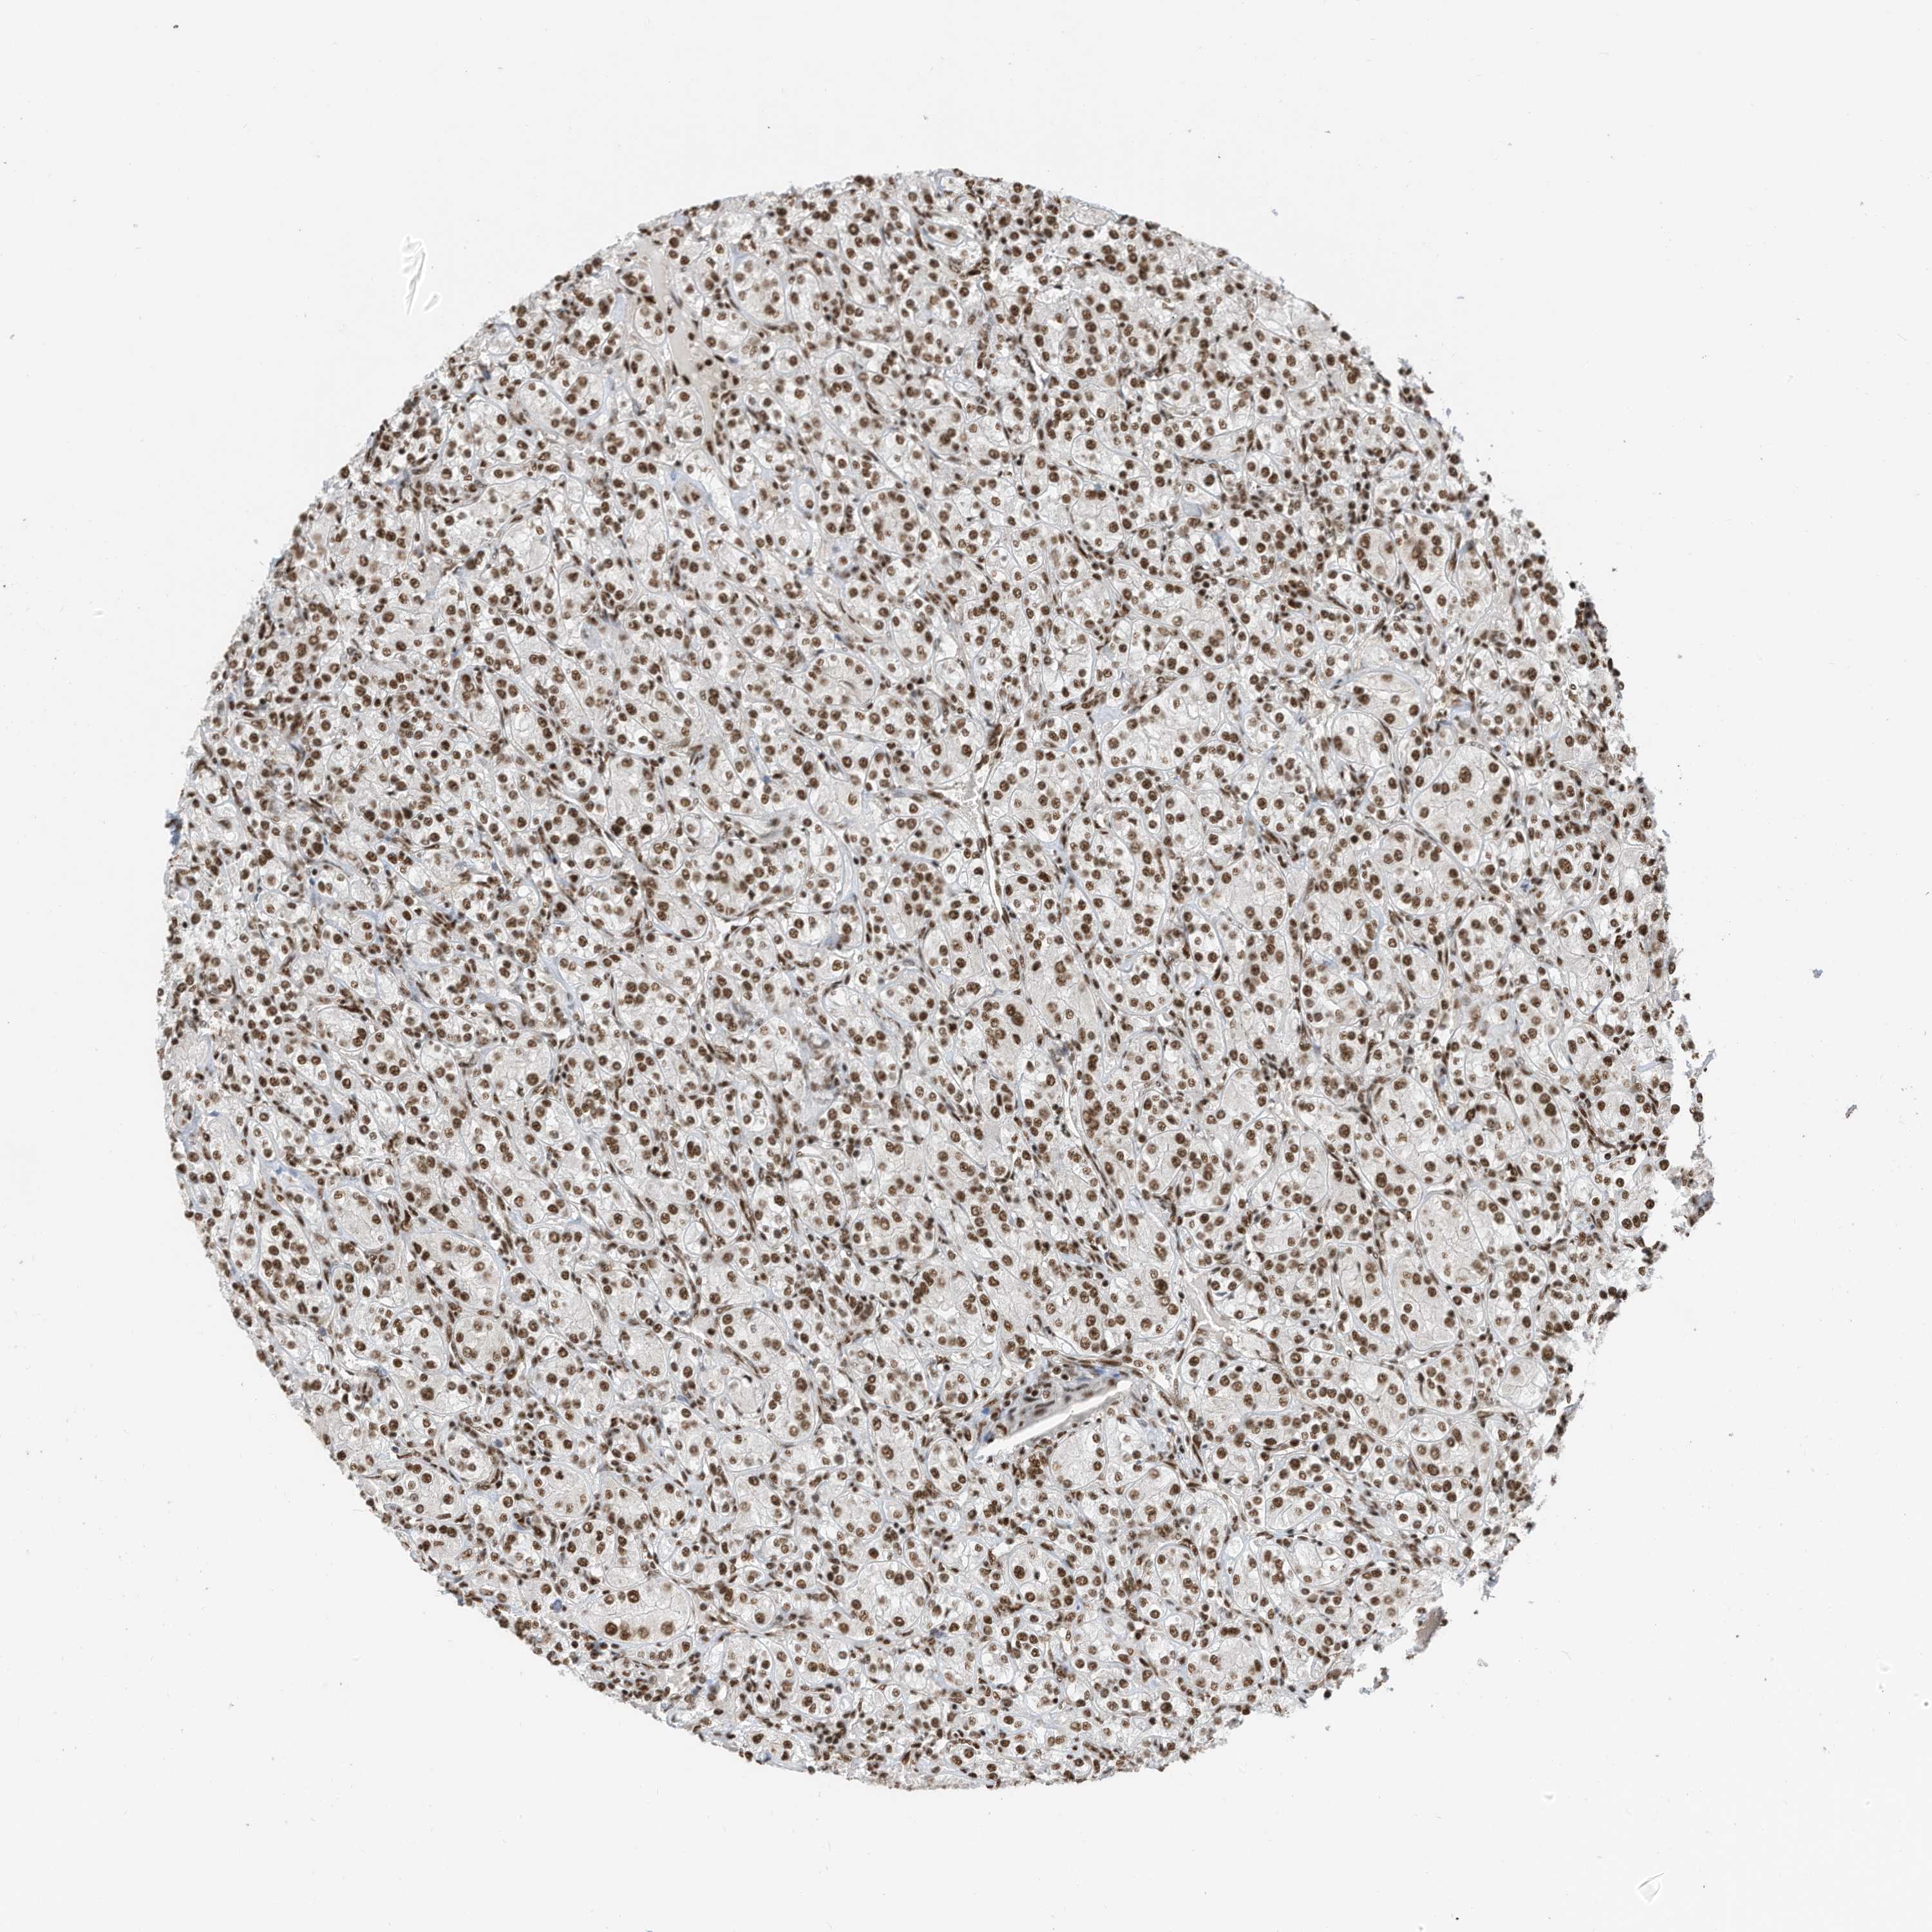

CANCER RENAL CANCER Show tissue menu

KICH TCGA KIRC TCGA KIRC VALIDATION KIRP TCGA PROTEIN RCC CPTAC PROTEIN EXPRESSION

KIDNEY CHROMOPHOBE (TCGA) - Interactive survival scatter ploti

The Survival Scatter plot shows the clinical status (i.e. dead or alive) for all individuals in the patient cohort, based on the same data that underlies the corresponding Kaplan-Meier plots. Patients that are alive at last time for follow-up are shown in blue and patients who have died during the study are shown in red.

The x-axis shows the expression levels (FPKM) of the investigated gene in the tumor tissue at the time of diagnosis. The y-axis shows the follow-up time after diagnosis (years). Both axes are complimented with kernel density curves demonstrating the data density over the axes. The top density plot shows the expression levels (FPKM) distribution among dead (red) and alive patients (blue). The right density plot shows the data density of the survived years of dead patients with high and low expression levels respectively, stratified using the cutoff indicated by the vertical dashed line through the Survival Scatter plot. This cutoff is automatically defined based on the FPKM cutoff that minimizes the p-score. The cutoff can be changed by dragging the vertical line or by entering a cutoff value in the square labeled "Current cut-off".

Under the Survival Scatter plot the p-score landscape (black curve; left axis) is shown together with dead median separation (red curve; right axis). Dead median separation is the difference in median mRNA expression between patients who have died with high and low expression, respectively. It is calculated as follows: median FPKM expression of dead patients with high expression - median FPKM expression of dead patients with low expression. This is intended to aid the user in visually exploring custom cutoffs and the associated p-scores and dead median separation.

Individual patient data is displayed and can be filtered by clicking on one or more of the category buttons on the top of the page. Categories describing expression level and patient information include: high, low, alive, dead, female, male and tumor stages. The scale of the x-axis can be toggled between linear and log-scale by clicking on the "x log" button. Mouse-over function shows TCGA ID, patient information and mRNA expression (FPKM) for each patient.

& Survival analysisi

Kaplan-Meier plots summarize results from analysis of correlation between mRNA expression level and patient survival. Patients were divided based on level of expression into one of the two groups "low" (under cut off) or "high" (over cut off). X-axis shows time for survival (years) and y-axis shows the probability of survival, where 1.0 corresponds to 100 percent.

SF3A3 is not prognostic in Kidney Chromophobe (TCGA)